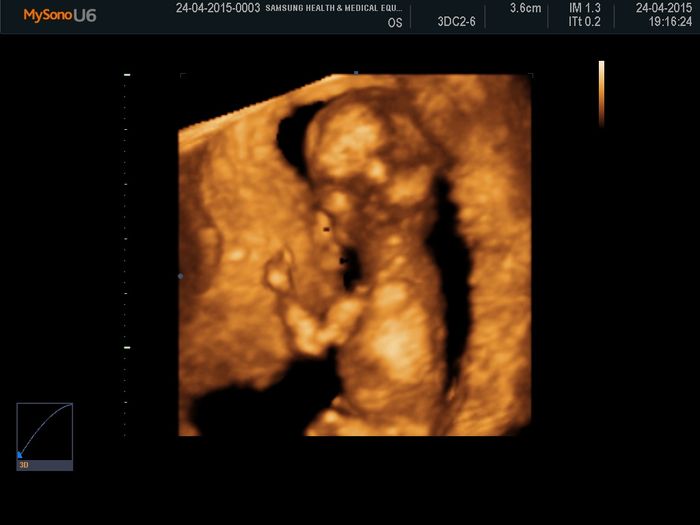

Buongiorno ragazze era da un po che non aprivo un topic e cosi ho deciso di farlo oggi, ieri siamo stati dalla ginecologa per l'ecografia di accrescimento della 31esima settimana.. il piccolo sta benone pesa gia 2 chili belli pieni pieni : (la...